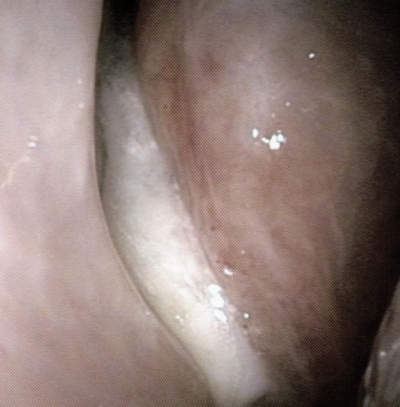

83歳の男性。 3か月前からの左顔面痛を主訴に来院した。痛みが強い時には夜も眠れないという。顔面の発赤、腫脹はない。他の神経症状を認めない。鼻腔と咽頭の内視鏡像及び副鼻腔 CTを別に示す。

上咽頭内視鏡像